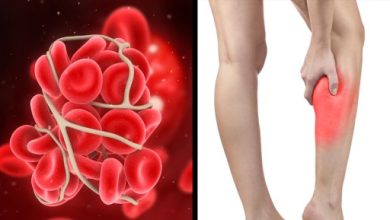

الجراحة والحمل أبرز أسباب الجلطات الوريدية.. أهم طرق الوقاية

تزداد فرص الإصابة بالجلطات في الأوردة بناء على العديد من الأسباب التي ربما تكون غير معروفة لدى الكثيرين، وخلال الأسطر…